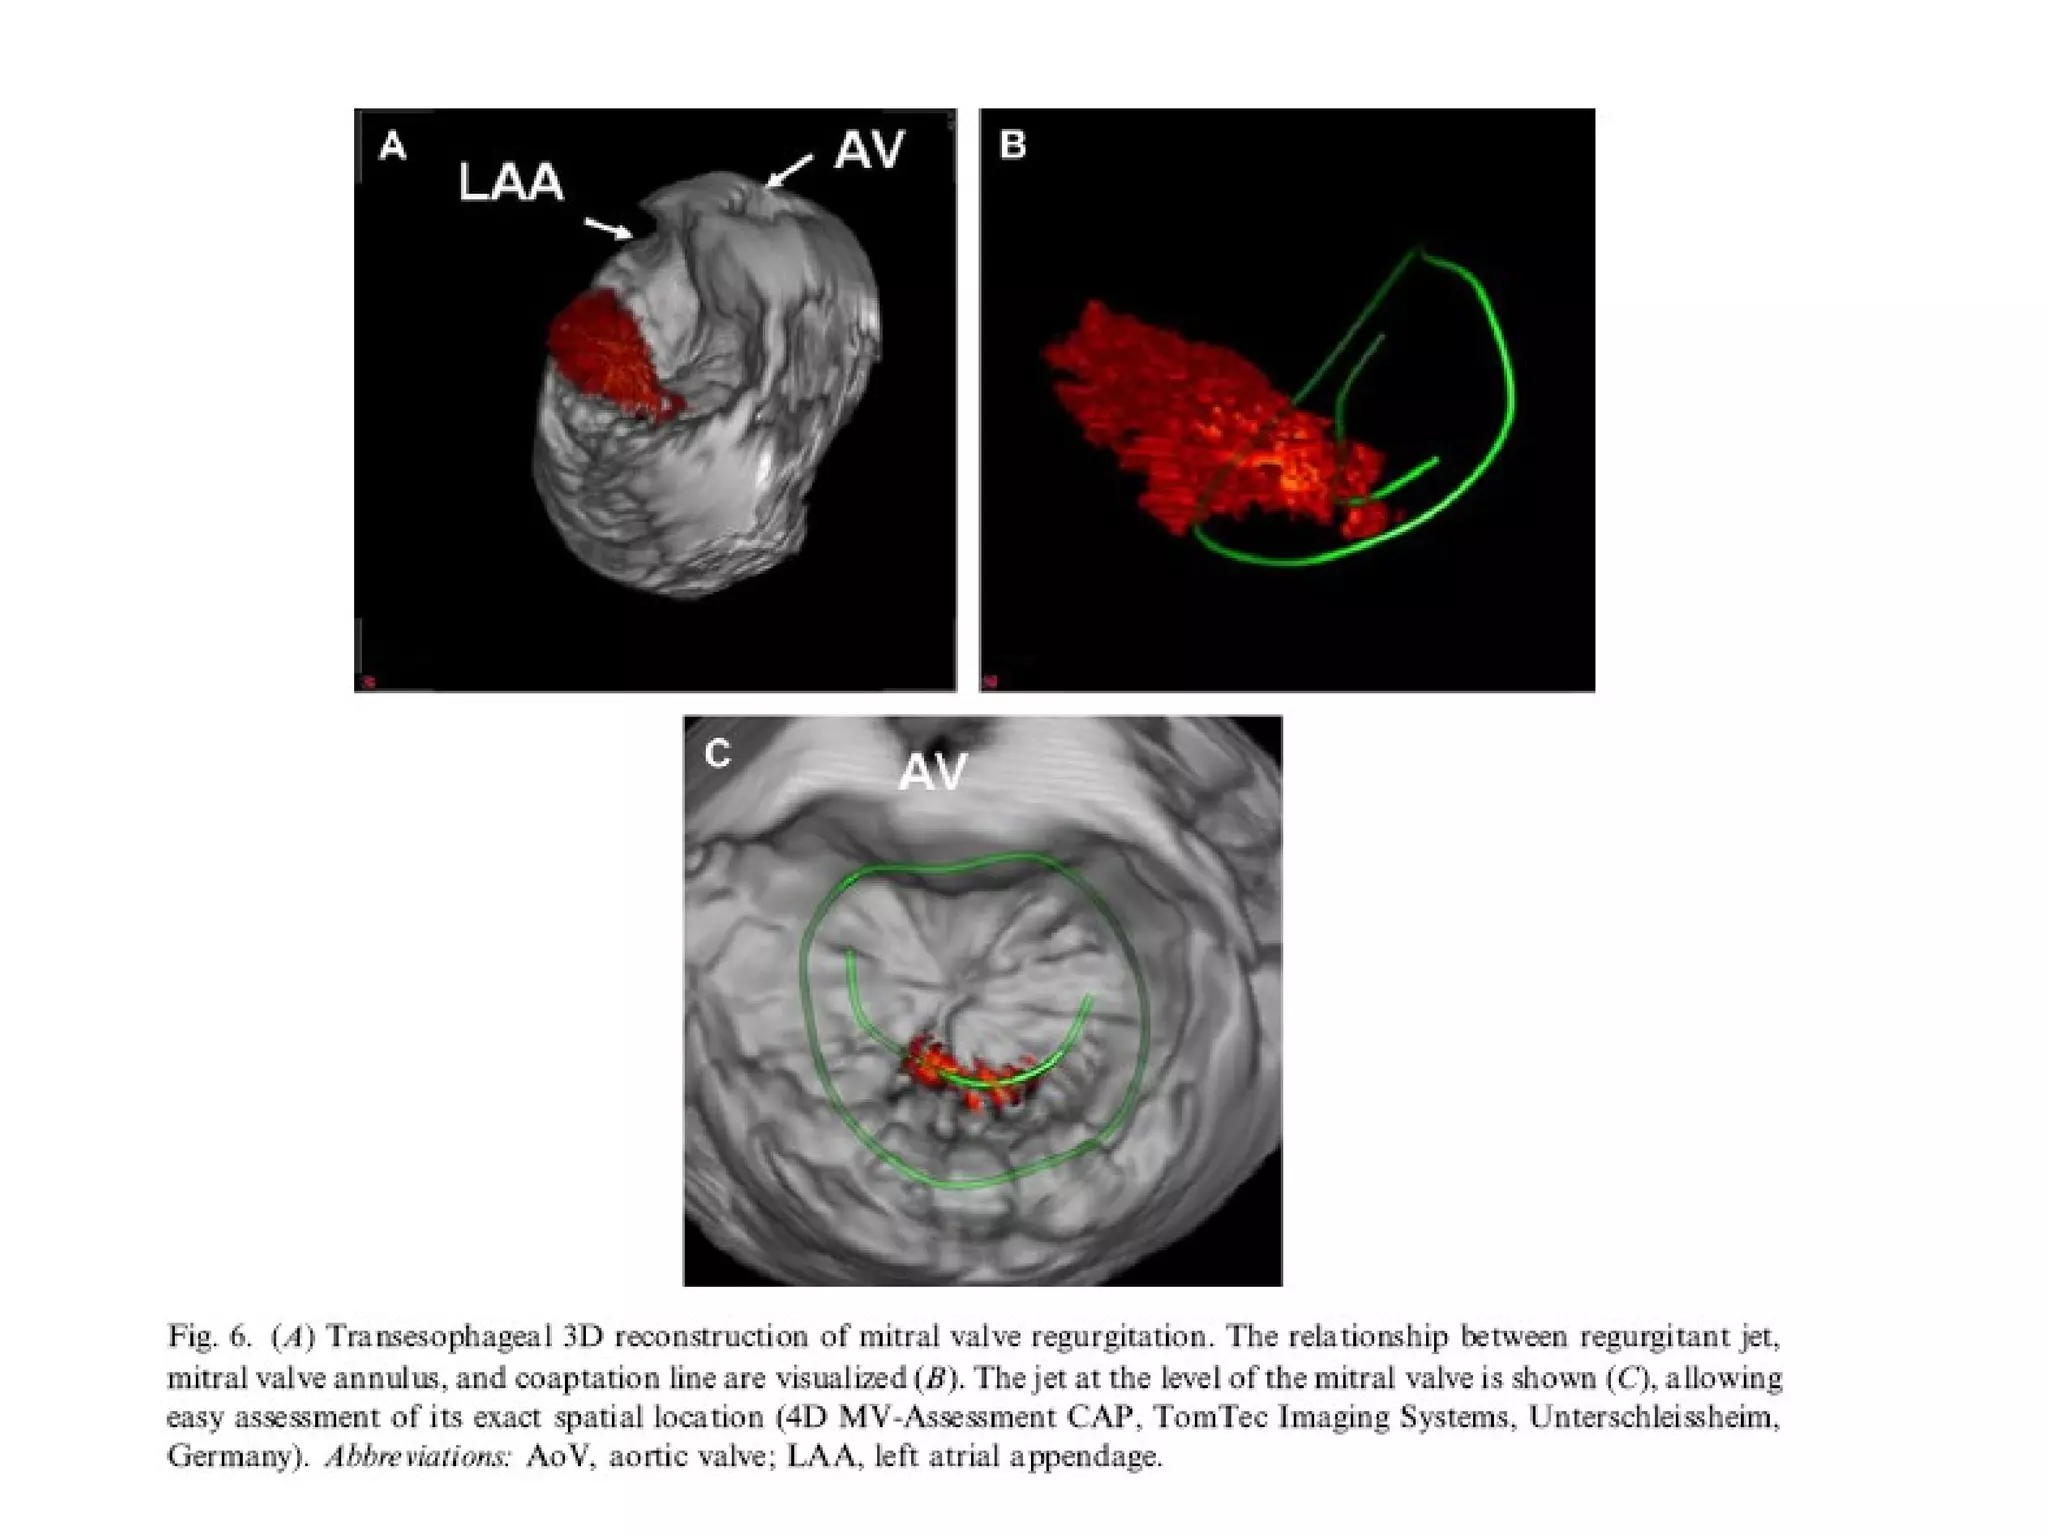

been done on

echocardiography

• 1) Directevaluation of cardiac chamber volumes without the need for geometric modeling • 2) Noninvasive realistic views of cardiac valves and congenital abnormalities , helpful for showing a variety of pathologies and assessing the effectiveness of surgical or percutaneous transcatheter interventions • 3) Direct3D assessment of regional LV wall motion aimed at objective detection of ischemic heart disease at rest and during stress testing ,as well as quantification of systolic asynchrony to guide ventricular resynchronization therapy • 4) 3D color Doppler imaging with volumetric quantification of regurgitant lesions shunts ,and cardiac output • 5) Volumetric imaging and quantification of myocardial perfusion

• Most studieshave been done on mitral valve. Understanding about the mitral valve annulus, leaflet tethering, tenting volumes has improved with the advent of 3 D echocardiography